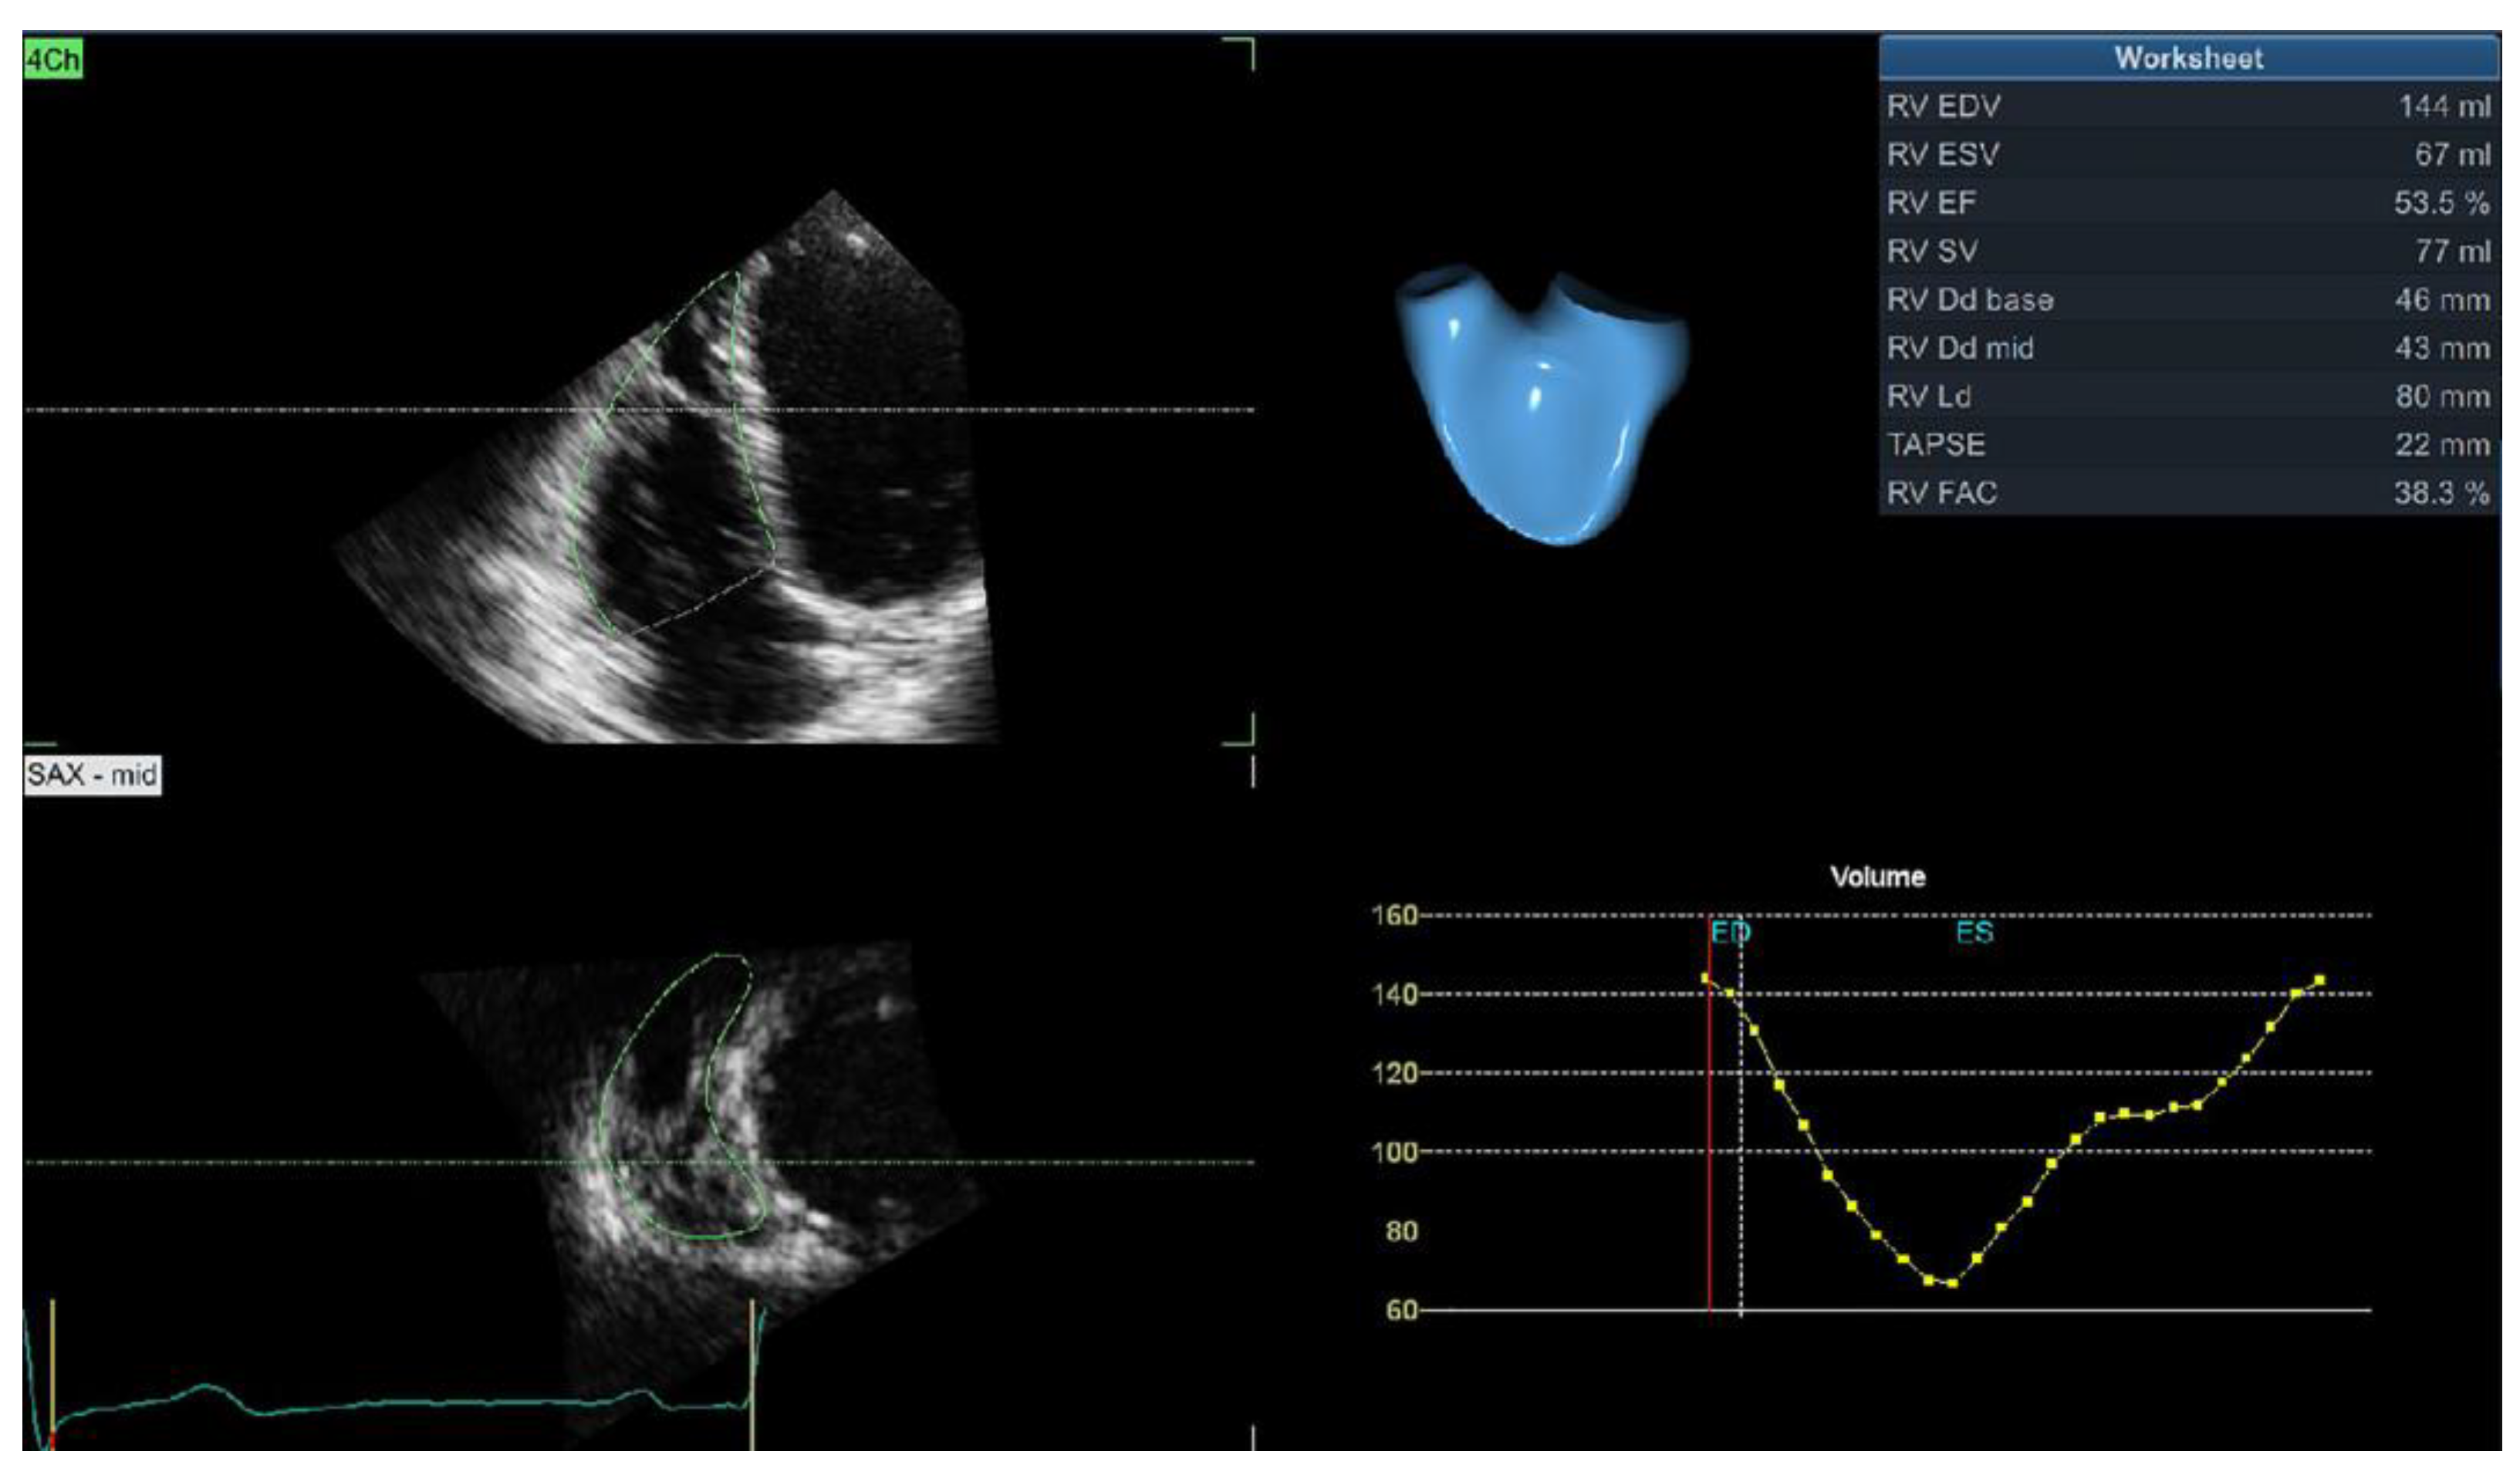

Most of the published data showed no difference in conventional 2D echocardiographic parameters (TAPSE, s’, and FAC) between hypertensive and normotensive subjects [19,26,27]. However, new imaging modalities have revealed the deterioration of RV systolic function in hypertensive patients. Our study showed significantly reduced 3D RVEF in hypertensive patients [19]. We also reported that LV geometry has a significant impact on 3D RV volumes and RVEF and found that hypertensive patients with dilated LVH and combined concentric-dilated LVH had significantly lower 3D RVEF than hypertensive patients with normal LV geometry, concentric remodeling, and concentric or eccentric LVH [28]. Impaired RV systolic function is a predictor of adverse events in the hypertensive population, but its predictive importance vanishes after an adjustment for other clinical and echocardiographic parameters [5]. Figure 1 shows the 3D echocardiographic assessment of RV volumes and the ejection fraction.

Figure 1.

3D echocardiographic evaluation of right ventricular volume and ejection fraction.